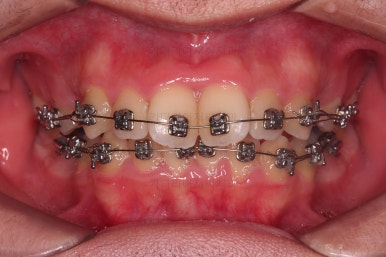

총 19개월만에 치료를 종료했습니다.

가지런한 느낌, 교합, 중앙선 등 매우 양호한 치료결과였습니다.

전후 비교입니다.

입은 약간만 들어가게끔 했고요.

웃을 때의 입매가 참 좋아졌네요.

얼굴모습에서 드러나는 치열의 느낌이 매우 좋아졌어요.